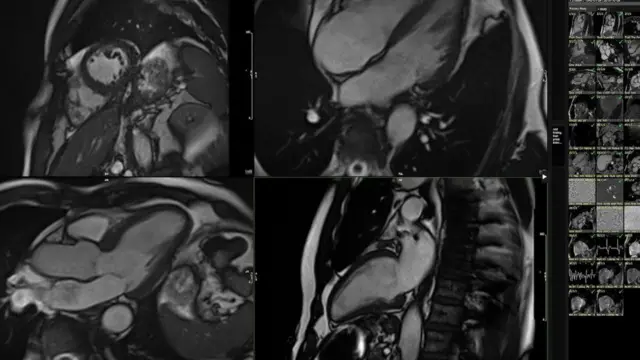

దీని కోసం వ్యాయామం తర్వాత నా గుండెకు మ్యాగ్నెటిక్ రీసొనెన్స్ ఇమేజింగ్ (ఎంఆర్ఐ) స్కాన్ను చేయించాల్సి ఉంటుంది.

3డీ మోషన్లో నా ఎంఆర్ఐ స్కాన్కు సంబంధించిన వేల కొద్ది సూక్ష్మ వివరాలను ఈ టూల్ విశ్లేషించింది. భిన్న వయసు గల 5000 మంది ఆరోగ్య వంతుల సమాచారంతో దీన్ని సరిపోల్చింది.